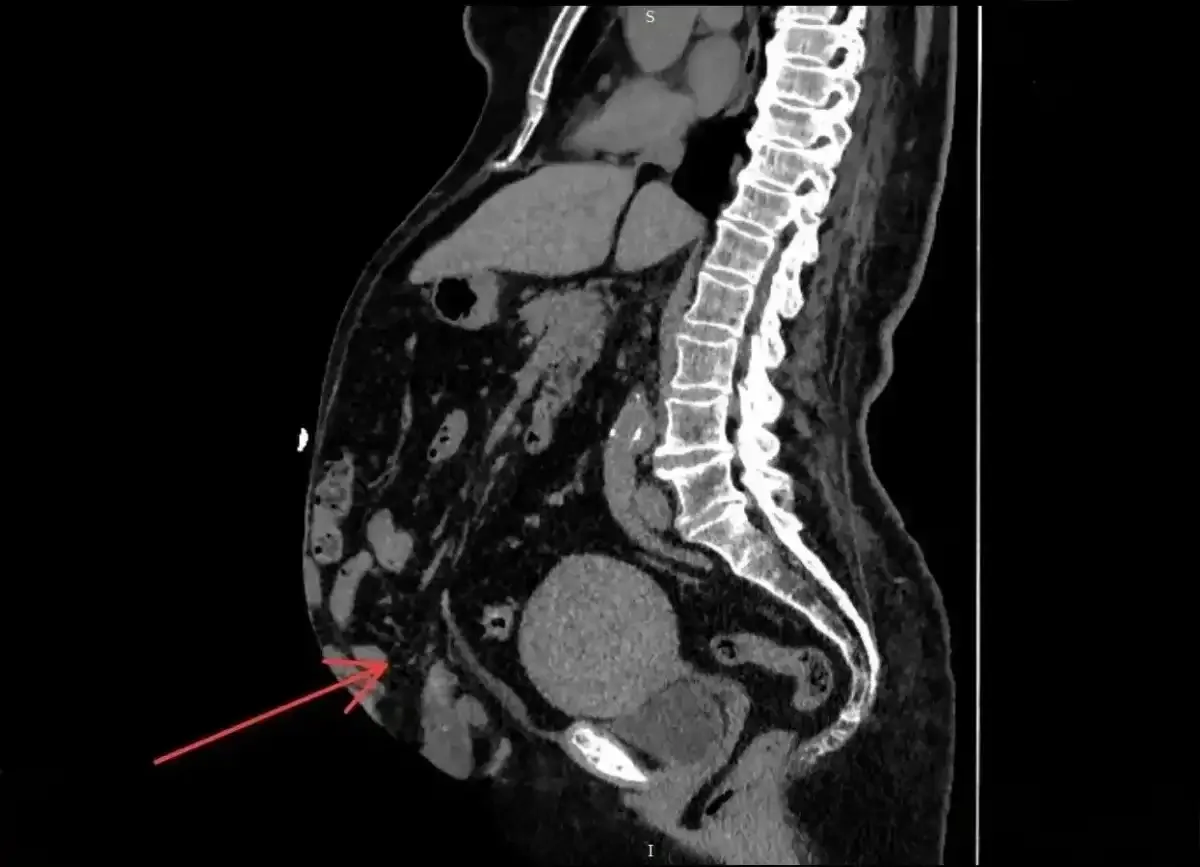

70-летняя жительница города Холм столкнулась с грыжей не в первый раз. Несколько лет назад ей удалили пупочную грыжу, затем произошёл рецидив послеоперационной грыжи. Со временем грыжа вернулась и достигла большого размера.

Было принято решение выполнить ненатяжную пластику с полной реконструкцией брюшной стенки.